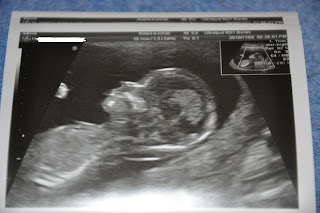

Det ligger några nya utmaningar framför oss under 2011, den största av dem är nog tillskottet i familjen. Nu börjar vi närma oss halvtid!!